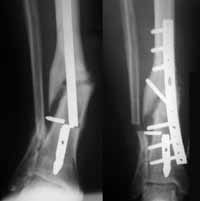

Hubo dos casos de deformidades posoperatorias en valgo (10° y 12°), ambas en el grupo de clavos no fresados. La primera a nivel de diáfisis distal que progresó en los controles subsiguientes, requiriendo reintervención hacia la octava semana del posquirúrgico para retiro de pernos, realineación de la diáfisis y osteosíntesis de la fíbula distal, consolidando hacia las 18 semanas, sin secuelas (Figura 3). La segunda, una fractura del tercio medio que consolidó con 12° de valgo, sin alteración funcional.

Figura 3. Deformidad posquirúrgica en valgo, que requirió reintervención y osteosíntesis de la fíbula distal.